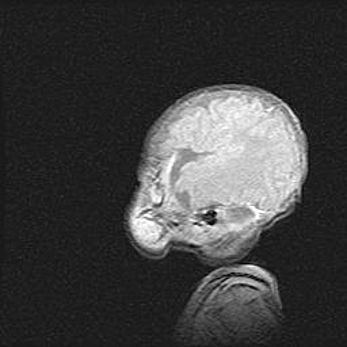

мрт снимки

Ниже представлена  галерея МРТ снимков, полученных с применением LMT неонатальных матричных РЧ катушек. Также каждая группа МРТ снимков сопровождается информацией о пациенте (диагноз, возраст, вес, пол, срок гестации) и краткой сопроводительной расшифровкой диагноза.

Церебральная ишемия II.

Возраст: 5 дней

Вес: 3400 г

Пол: женский

Окружность головы: 35 см

Срок гестации: 39 недель

Церебральная ишемия – это заболевание, характеризующееся недостаточностью (гипоксией) либо полным прекращением (аноксией) снабжения мозга кислородом по причине закупорки одного или нескольких сосудов. Это приводит к  что метаболическим расстройствам различной степени тяжести в тканях головного мозга, развитию коагуляционных некрозов и гибели нейронов.